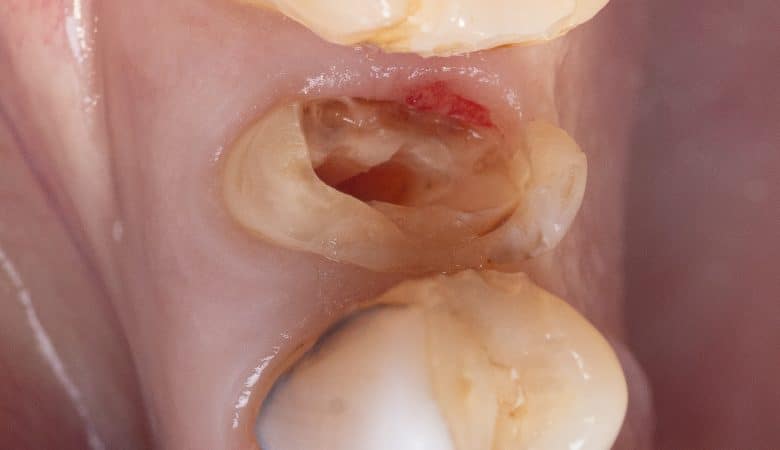

Restoring badly destructed upper first molar as part of a full mouth rehabilitation Root canal treatment with (periapical lesion & retreatment) + Deep marginal elevation + Overlay preparation done with passion & love My Surface treatment protocol for the tooth…

Technique: Deep margin elevation

Deep margin elevation (DME) This is a restorative clinical procedure consisting of raising approximately 2 mm with resin the margins that were below the gum, with the intention that they are visible to be able to seal on them our…